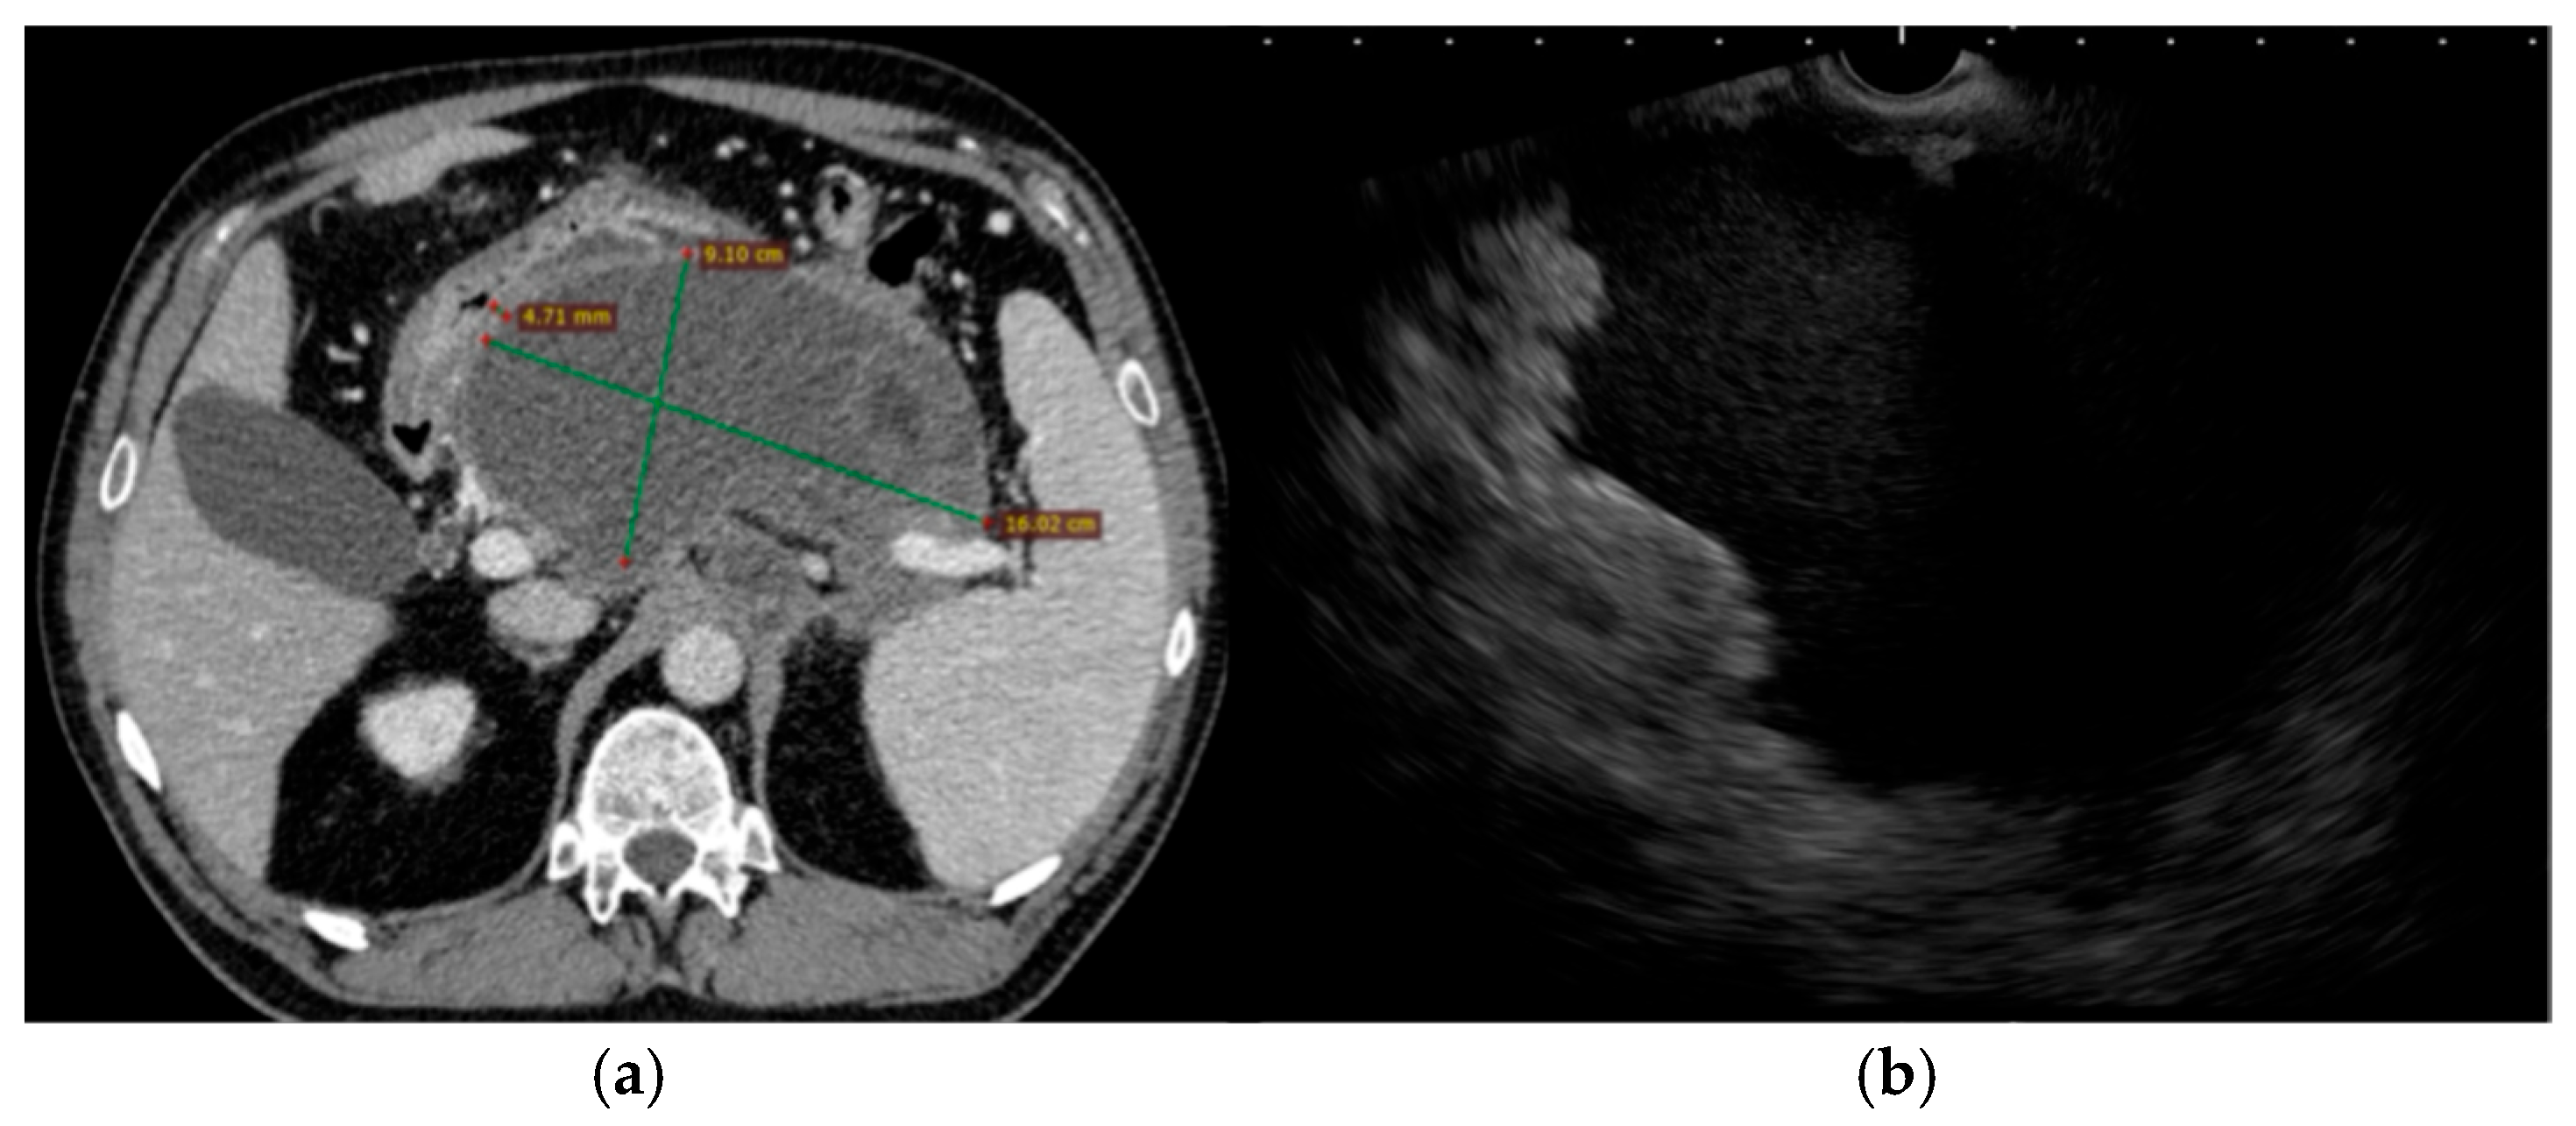

Clinical course: The patient was admitted with acute cholangitis and spontaneous stone passage complicated by secondary biliary pancreatitis. The onset of symptoms has been reported to occur within under 24 h before admission. Presepsin at admission reached 1200 pg/mL, and procalcitonin was 0.75 µg/L. Despite supportive and antibiotic therapy with imipenem–cilastatin 500 mg IV every 8 h, she developed persistent fever, abdominal discomfort, and an ongoing inflammatory response. Contrast-enhanced CT scan within 72 h of admission reported an mCTSI score of 8 and revealed a large (9 × 16 cm) retrogastric peripancreatic collection with necrotic components and a mature wall consistent with a WON (Figure 3). No pseudoaneurysms were observed. Moderately dilated bile ducts have also been described.

Figure 3.

Pre-intervention imaging evaluation. (a). Abdominal CT scan showing a large peripancreatic retrogastric WON (with approximately 30% necrosis) with no parietal pseudoaneurysms, but with marked gastric and mesenteric compression; (b). Trans-gastric EUS image of the same collection of fluid.